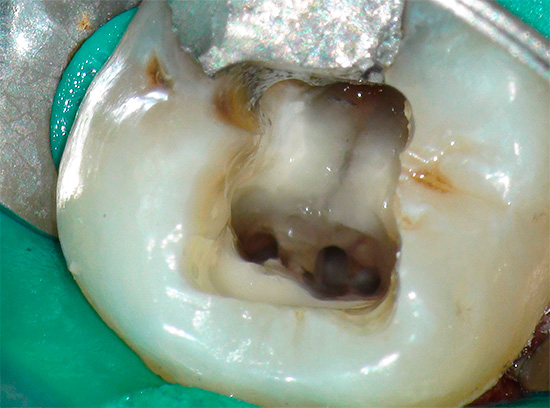

Ed è così che appare il trattamento della carie profonda al microscopio, tutti gli stadi sono ben tracciati